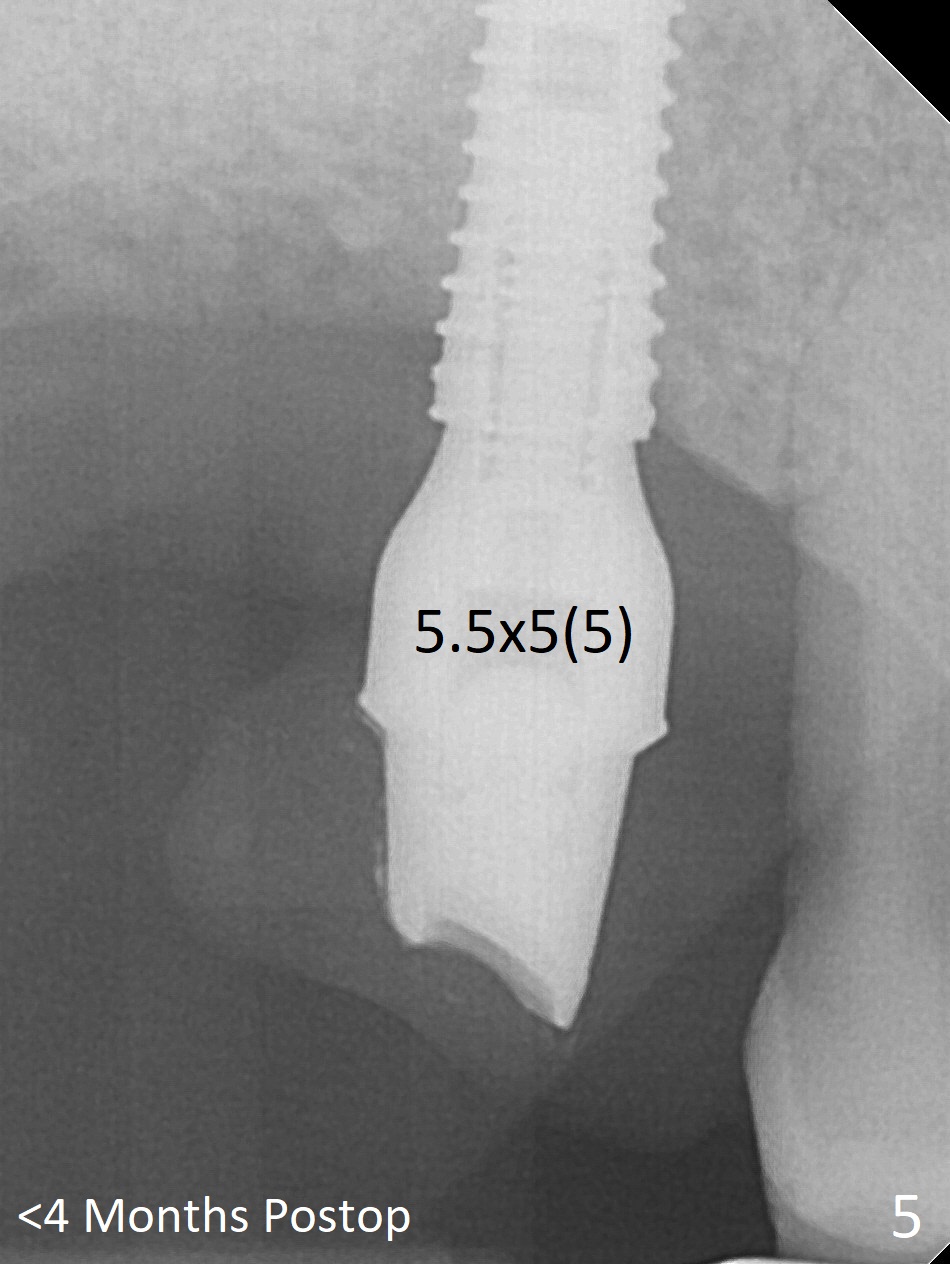

Since the ridge crest at #3 is narrow, Tatum bone scalpels are used to get access and initiate bone expansion, followed by bone blades and RT 2. It seems that the osteotomy starts mesially; bone height being increased (Fig.1). When the apical end of the osteotomy tilts mesially, more bone height is obtained. Drills are alternatively applied because of the hard bone (Fig.2). A 4x13 mm UF implant is placed initially with the distal threads unburied (Fig.3, >50 Ncm). With further seating of the implant, a 5.5x5(4) mm abutment is used (Fig.4), which closes the access. No suture is warranted. An immediate provisional is fabricated for the patient's comfort and psychological effect. In fact, the abutment cuff changes to 5 mm prior to temporarization. There appears no bone loss <4 months postop (Fig.5). Pulpitis develops at #4 due to DO caries 1 year 5 months post cementation (Fig.6 *). The crown at #3 is removed for easy and conservative distal carious removal and Cavit temporary restoration to prevent sodium hypochlorite leakage. Then occlusal access is made for pulpotomy. When RCT finishes, no crown will be made, but occlusal reduction is required. The patient returns for RCT 1 month later (Fig.7,8). Cavit remains in place (Fig.7 C). Although 2 threads are exposed distal (Fig.8 arrow), there is no sign or symptom of periimplantitis, which may be related to the thick gingiva (arrowhead). Return to Upper Molar Immediate Implant, IBS, #14 (Tissue Punch) Xin Wei, DDS, PhD, MS 1st edition 08/25/2017, last revision 09/08/2019